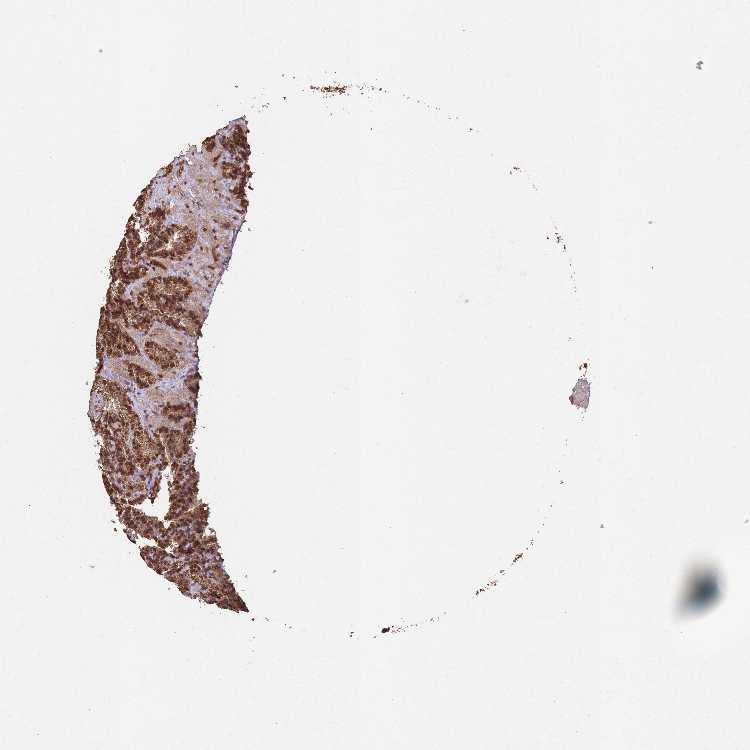

SEMINAL VESICLE - Antibody stainingi

Antibody staining in the annotated cell types in the current human tissue is reported as not detected, low, medium, or high, based on conventional immunohistochemistry profiling in selected tissues. This score is based on the combination of the staining intensity and fraction of stained cells.

Each image is clickable and will lead to virtual microscopy that enables deeper exploration of all samples and also displays staining intensity scores, fraction scores and subcellular localization as well as patient and tissue information for each sample.

Antibody CAB045977

Glandular cells High